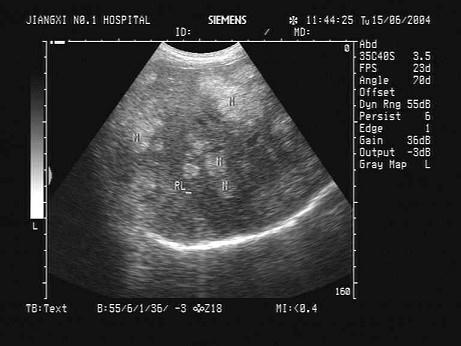

问题 某患者二年前行左肾癌切除术,现B超复查。根据其肝脏超声声像图,诊断为?(?)

选项 A.肝多发血管瘤 B.肝多发转移癌 C.原发性肝癌 D.结节性肝硬化 E.肝多发性囊肿

答案 B